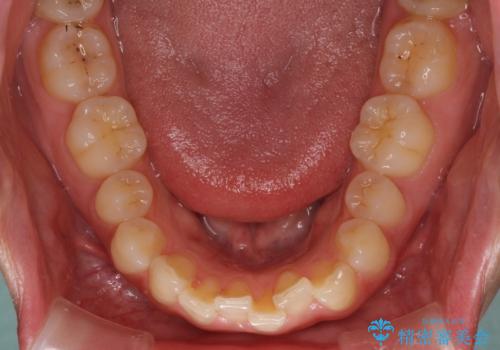

インプラントによる補綴治療とインビザライン矯正

- 抜歯が必要と診断された奥歯を気にして来院された患者様です。

抜歯の上インプラントによる補綴治療を行うこととなりましたが、前歯の叢生も気になるとのことで並行して矯正治療を行うこととしました。

歯列不正は軽微であったので、インビザラインによる矯正治療とし、矯正治療中にインプラント埋入を行う予定としました。

痛みがないので、ボロボロのまま放置していましたが、抜歯後は汚れが溜まりにくくなりスッキリとしたようです。

前歯のデコボコも解消され、ブラッシングが楽になりました。